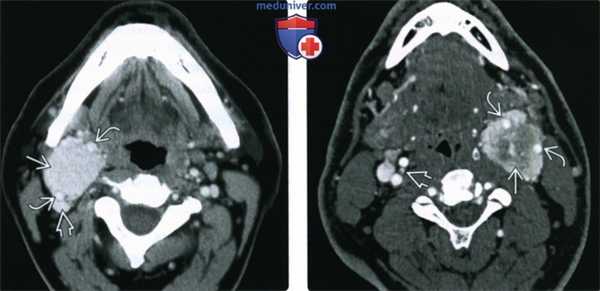

(а) Аксиальная, (б) фронтальная и (в) сагиттальная проекция КТ шеи с контрастированием. Определяется новообразование в области сонного влагалища, интенсивно накапливающее контраст, неоднородной плотности, раздвигающее наружную и внутреннюю сонные артерии.

Наиболее явно последний признак виден на МР-ангиографии (а). В опухоли проходит множество быстро наполняющихся артериальных сосудов.

Данные лучевых методов диагностики соответствуют параганглиоме/опухоли каротидного синуса, которые могут развиваться на любом участке хода симпатических волокон.

Обычно их отличают ровные контуры и интенсивное накопление контраста за счет высокой васкуляризации.

На МРТ возможно присутствие признака «соли и перца», обусловленного наличием участков потери сигнала. Ангиография показывает интенсивную васкуляризацию опухоли.

Данный случай отличает наличие метастатических поражений (в том числе верхнего отдела грудной клетки со сдавлением грудного отдела спинного мозга), которые можно увидеть на сагиттальных проекциях в режимах Т1 (б) и Т2 (в).

Гистологическое исследование метастазов в спинном мозге подтвердило их происхождение от параганглиомы.